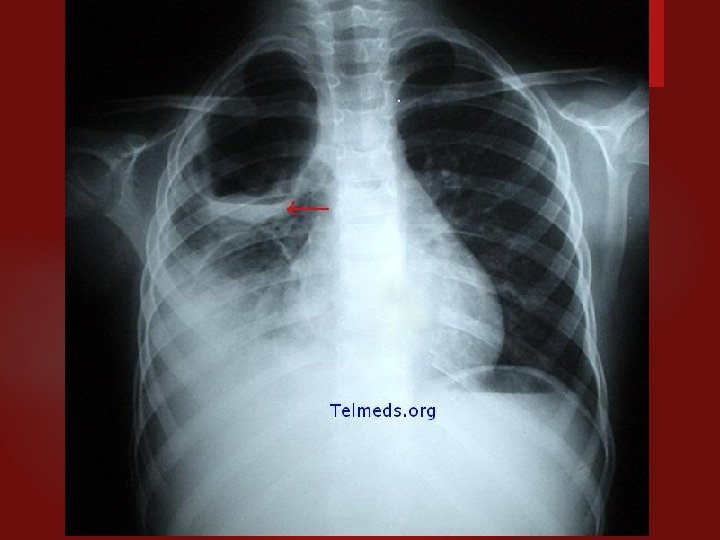

PNEUMONÍA STAPHILOCOCCUS AUREUS

NEUMONIA AGUDA Caracteristicas clínico-radiológicas Etiología bacteriana: consolidación lobar, cavitación y derrame pleural. Compromiso difuso bilateral: etiología viral, neumonía atípica y por pneumocystis carinii. Staphylococus aureus: de focos múltiples, neumatoceles. Legionella: de focos múltiples, progresión radiológica rápida. Necrotizante, con abscesos o empiema: por gramnegativos, estafilococo, por anaerobios.